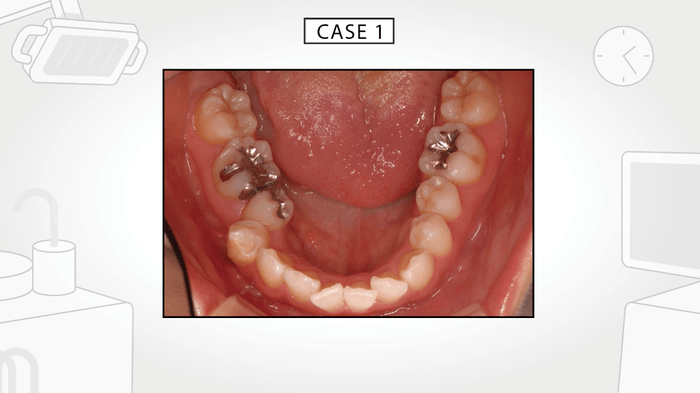

今回発表した動画は、それらの不定愁訴を引き起こしている原因が口内の舌の緊張によるものであることを示し、さらに、その要因は現代人の食生活が引き起こした顎や歯に見られる身体的特徴ということを解説しています。